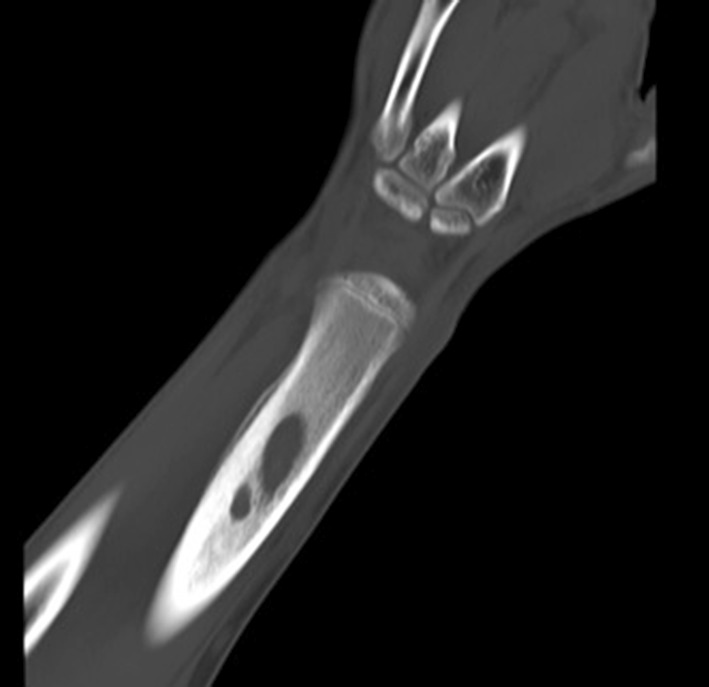

Fig. 4.

CT scan of the left distal radius confirming the lucent area with cortical thickening